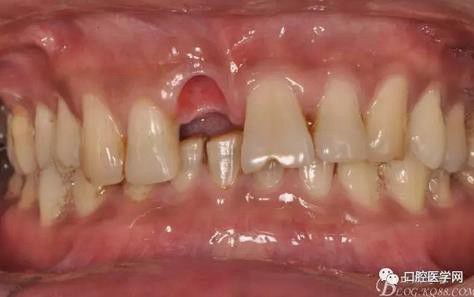

圖4 術(shù)前正位頜面照

圖5 拔除殘根

圖6 術(shù)中植入植體